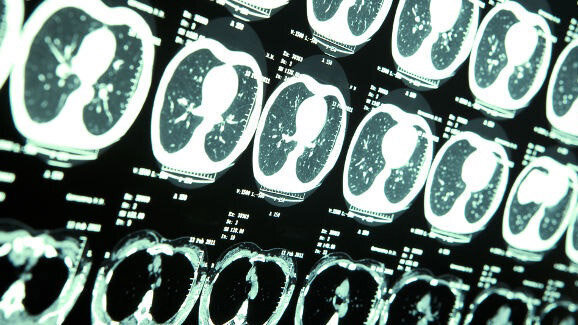

TAIWAN – Diagnostische dentale röntgenfoto’s zorgen niet voor een hoger risico op kwaadaardige hersentumoren. Dat concluderen Chinese wetenschappers. In eerdere onderzoeken is wel aangetoond dat frequente dentale en medische screening zorgt voor een vijf maal grotere kans op een goedaardige hersentumor.

De wetenschappers hebben in twee onderzoeken gekeken wat het verband is tussen goedaardige en kwaadaardige tumoren en het aantal dentale röntgenfoto’s tijdens orale en maxillofaciale zorg. Bij het eerste onderzoek werden 4123 patiënten met een goedaardige tumor en 16.492 gezondheidscontroles geanalyseerd. Het tweede onderzoek werd uitgevoerd onder 197 patiënten met een kwaadaardige hersentumor die 788 controles hadden ondergaan.

Uit analyse van de onderzoeksdata bleek dat het risico op een goedaardige hersentumor toenam naarmate de frequentie van diagnostische dentale röntgenfoto’s groter was. Tussen kwaadaardige hersentumoren en blootstelling werd geen verband gevonden.

Het onderzoek werd uitgevoerd aan de China Medical University, in samenwerking met verschillende andere wetenschappelijke gezondheidsorganisaties in China. Het onderzoek is in februari gepubliceerd in Annals of Oncology.

De American Brain Tumor Association verwacht dat in 2013 69.720 nieuwe hersentumoren worden gediagnosticeerd, waarvan 24.620 kwaadaardig en 45.100 goedaardig. Bij 34% van de tumoren gaat het om meningeomen, vaak goedaardige hersentumoren. (bron: Dental Tribune International)